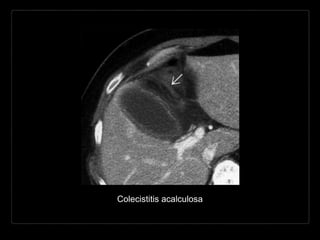

Hallazgos por TC

• +C

• dilatación intra- y extrahepática

• dilatación asimétrica de los conductos

intrahepáticos

Colecistitis acalculosa